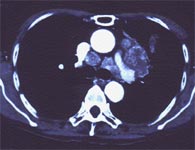

小細胞肺がんは小型の細胞からなる肺がんです。増大が早く大きなリンパ節転移を起こすので巨大な病変になります。肺がんのなかでもっとも治療の難しいがんです。男性に多く喫煙とも関係があります。肺門型と肺野型と両方認められます。

進行した時点で発見されるので手術の対象になることはまれですが、肺がんの中でもっとも放射線療法や化学療法に対して効果が認められます。

腫瘍マーカーで有効なのはNSEやProGRPです。CEAも上昇することがあります。

胸部CT写真です。中央にある白い丸は大動脈で長細いところが肺動脈と上大静脈です。その近くにある丸い青白いのが肺がんのリンパ節転移です。